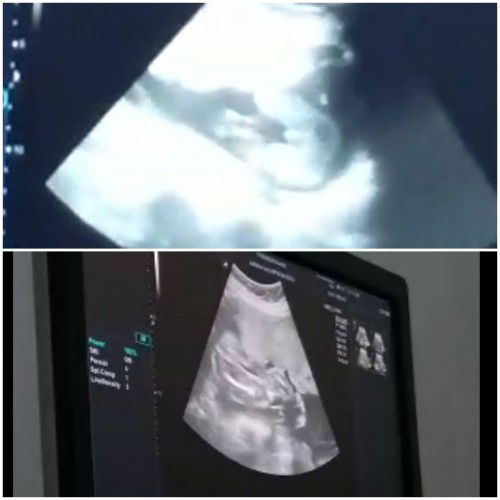

Mau sedikit cerita dan berbagi pengalaman 😁 jadi pas sebelum nikah pernah periksa sebelum nya ke puskesmas dan di bilang vaginitis. Langsung disitu ada rasa cemas takut nanti gabisa punya anak atau susah nanti punya anak nya. Gak lama saya menikah, suami udah tau dan gak masalah. Setelah nikah aku langsung cari2 info promil nonton youtube promil dan kebanyakan ikhtiar nya minum susu prenagen esensis sama folavit. Akhirnya mutusin buat langsung ngejalanin semua nya minum yg di anjurkan. Bulan berikutnya setelsh nikah masi dapet haid rasa nya sedih bgt pgn cepet2 pokonya. Bulan berikutnya telat haid 2 hari seneng bgt langsung beli tespack banyak subuh2 tapi garis nya 1 sedih cek terus2an sampe telat seminggu masi 1 garis. Tiba2 malem2 ngeflek warna pink gitu udah pasrah mau haid lagi pasti. Tapi cuma flek2 ajah ga keluar darah haid flek selama seminggu besok nya di taspack masi negatif juga. Mutusin buat ikut keluarga liburan kepuncak bawa motir sendiri bonceng sepupu karna suami kerja sampe di puncak renang main trampolin emng di kira haid :D ternyat pulang dari puncak pagi2 tes udah tutup mata eh ko ada garis samar di sebelah nya tpi samar bgt. Siangan dikit cek sama hasil nya samar. Dan alhamdulillah setelah 2 minggu telat meskipun garis nya samar langsung ke bidan buat usg dan udah ada kantong nya dan usia nya sudah 7 minggu langsung sujud syukur bahagia banget akhirnya yg di tunggu2 dateng juga. Nyesel bgt abis main trampolin wkwk. Gak nyangka bgt ternyata secepat itu allah kasi kepercayaan dan sekrang kebahagiaan semakin terasa utun udah 34 minggu tinggal menunggu launcing insha allah. Buat bunda2 semua yang lagi menunggu kehadiran buah hati. Bersabar ikhitar dan berdoa jgn lupa. Allah berikan di waktu yg tepat bukan yg tercepat insha allah. Semoga di lancarkan yg sedang promil atau sedang mengandung dan menunggu dede launching 😘😘😍#firstbaby #jangandibully #pregnancy